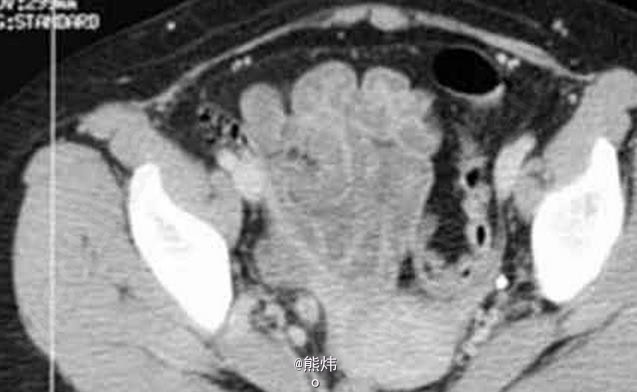

临床一例肾结核

肾结核

患者 女 30岁,因右腰疼痛1年前来就诊,既往无临床病史。

查:镜下血尿,尿培养阴性。伴有腰痛和发热 辅查造影

肾结核 处理:积极抗结核处理,采用链霉素